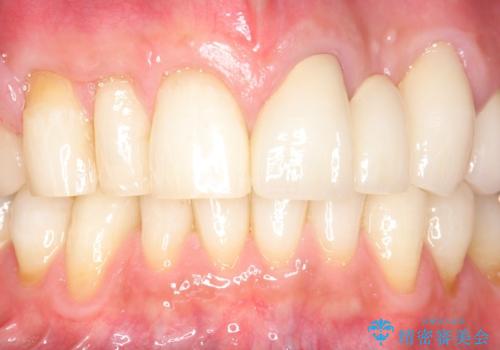

牽引により歯の保存が可能となり、ブリッジによる補綴を行うことができました。

健全歯質を歯肉縁上に出すためにしっかり挺出させたことで歯根長が短くなりましたが、仮歯で十分に保定した結果動揺度Ⅰ程度となり、ブリッジの支台歯にすることが可能と判断しました。

患者様には「抜歯適応の歯を残せて嬉しいし、とても丁寧に治療して頂けた」と大変喜んで頂けました。

クラウンの種類:オールセラミッククラウン スタンダード